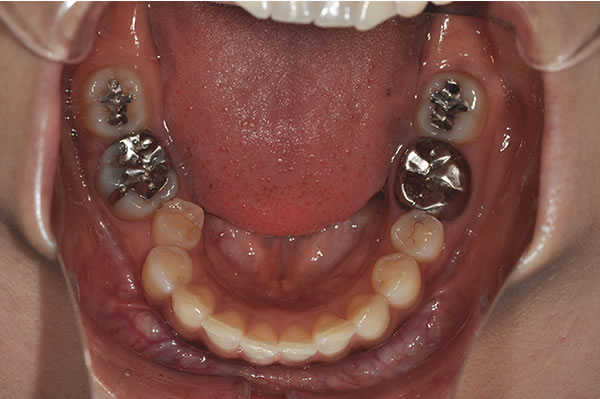

上顎前突症の治療例

上顎前突症(出っ歯)の矯正症例 ケース01

上顎前突症(出っ歯)の矯正症例 ケース02